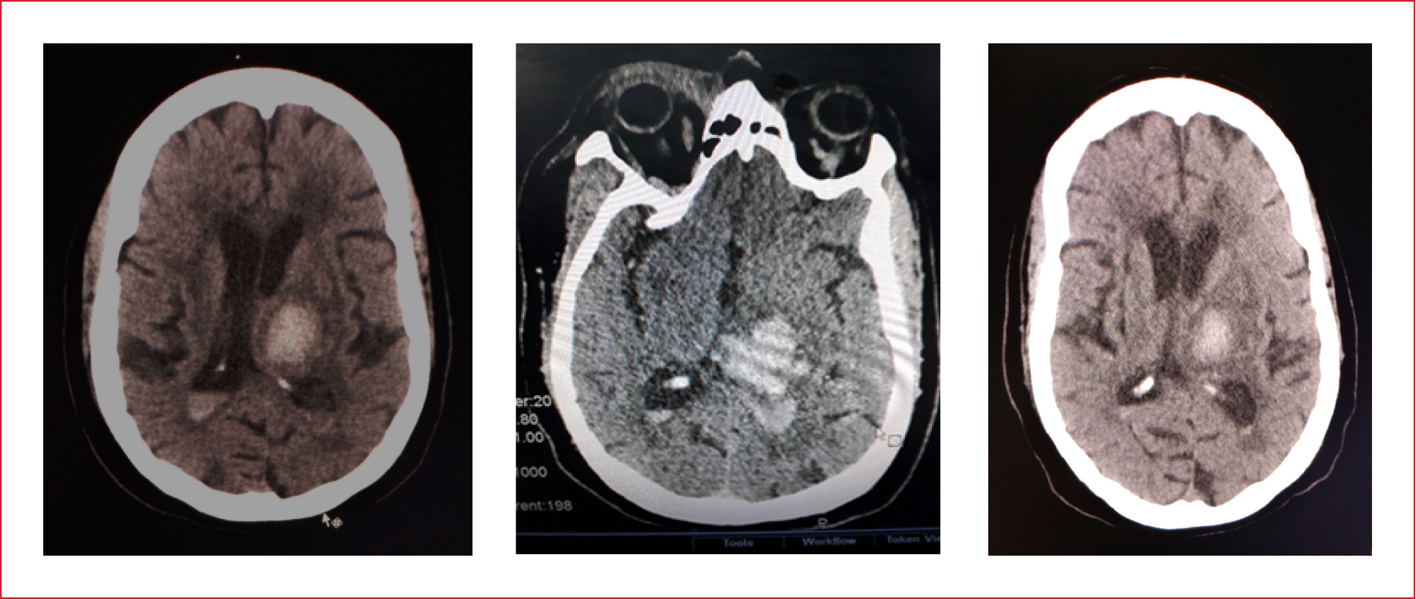

En la TC de cráneo (simple), se detectó una hemorragia intracraneal, de posible origen en el tálamo izquierdo, con extravasación en el ventrículo lateral izquierdo (Figura 1).

Figura 1. Tomografía computarizada de cráneo. Hemorragia intraparenquimatosa talámica izquierda abierta al sistema ventricular.

El diagnóstico de ingreso fue HIC espontánea no traumática, talámica izquierda con extravasación en el ventrículo lateral izquierdo y broncoaspiración de contenido gástrico (posible).

La TC de cráneo reveló una hemorragia talámica izquierda, sin edema cerebral y extravasación de sangre en los cuernos posteriores de los ventrículos, más en el izquierdo.